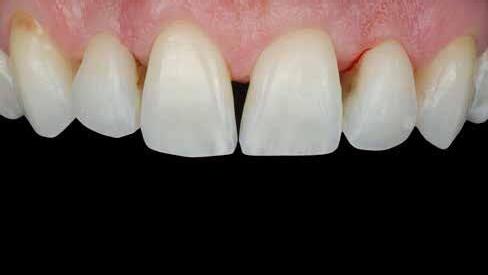

Egy 30 éves, negatív kórtörténettel rendelkező beteg azzal a kéréssel fordult hozzánk, hogy cseréljük ki az UR1 traumája után, 10 évvel korábban készült korábbi kompozit-helyreállítást.

A klinikai vizsgálat során az UR1 reagál a viabilitási tesztre, és az ugyanazon a napon készült röntgenfelvételen nem mutat periapikális elváltozásokat (1. ábra).

Az UR1 elszíneződött, és palatálisabb helyzetben van, mint az ellenoldali központi UL1 (2. ábra)

Az esztétikai elemzés a gingivális zenit aszimmetriáját mutatja az UR1 és az UL1 között. Parodontális szonda segítségével, plexusérzéstelenítés után, az IA

típusú funkcionális hám megváltozott passzív erupcióját igazoljuk Coslet és mtsai. osztályozása szerint (3. ábra)

A lehető legkonzervatívabb helyreállító kezelés elvégzése érdekében a páciensnél, figyelembe véve a megtartott fogelem korát és vitalitását, a tervezés és a diagnosztikai felviaszolás után a közvetlen kompozit-helyreállítás elvégzése mellett döntünk.